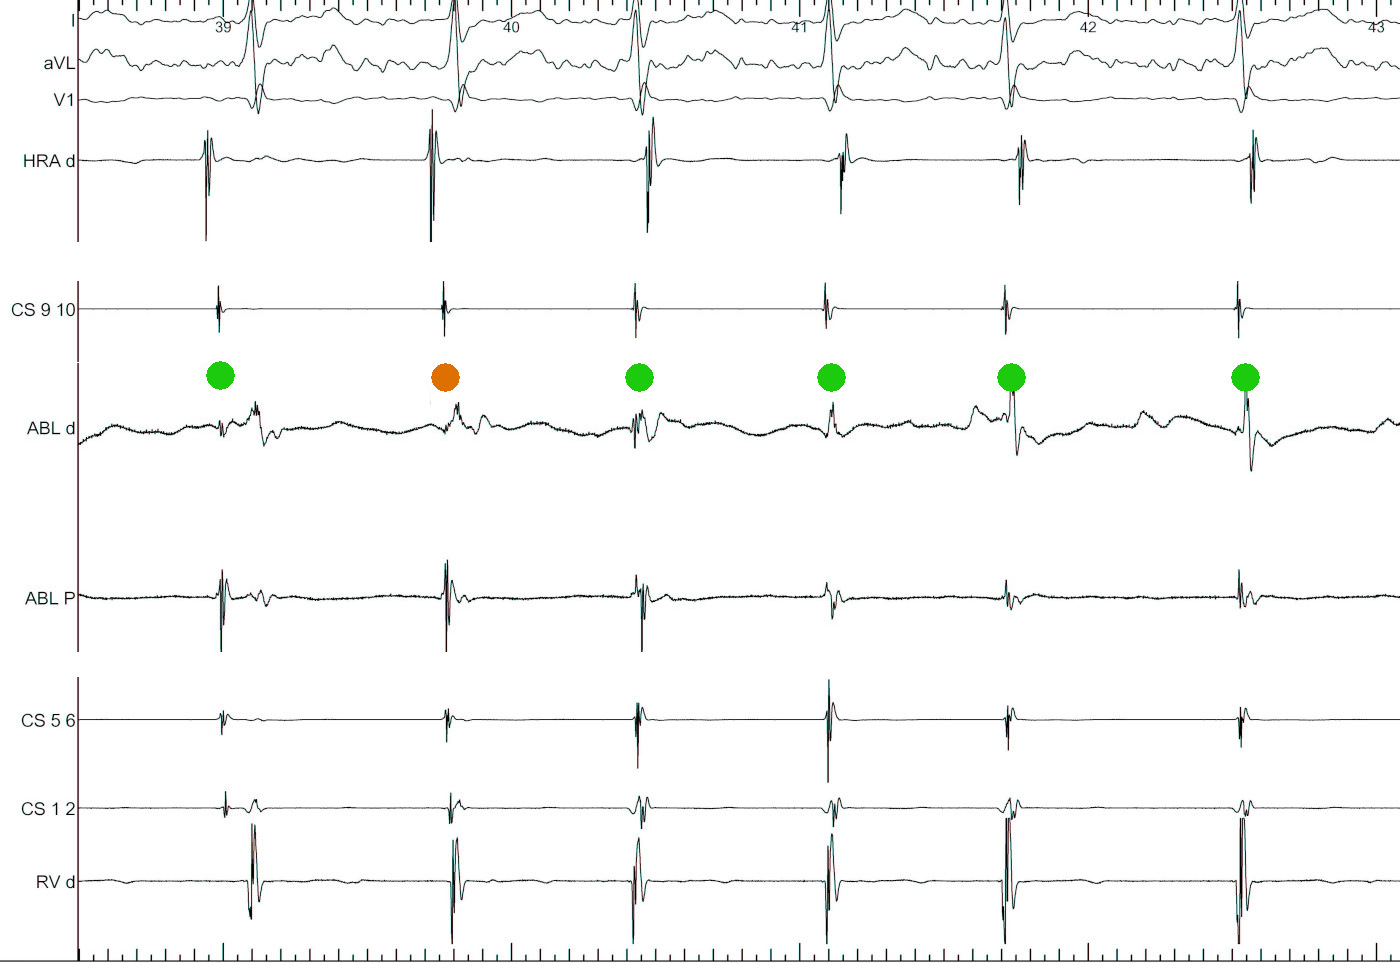

AVNRT or NV pathway mediated ORT - Case

1.jpg

Novel Approaches for the Diagnosis of Concealed Nodo-Ventricular and His-Ventricular Pathways. Satoshi Higuchi … Melvin Scheinman. Circulation: Arrhythmia and Electrophysiology. 2023;16 https://doi.org/10.1161/CIRCEP.122.011771

2.jpg